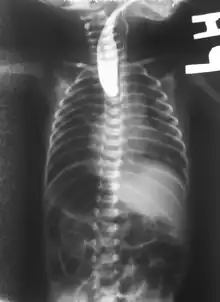

Plain X-ray of the chest and abdomen showing a feeding tube unable to move beyond an upper esophageal pouch.

On plain X-ray, a feeding tube will not be seen pass through the esophagus and remain coiled in the upper oesophageal pouch.[8]